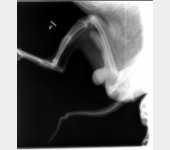

Leoś przebywał długie lata w schronisku w Raciborzu. Nikt Leosia nie chciał adoptować , taki był wycofany , bał się ludzi a w szczególności mężczyzn , co sami na sobie odczuliśmy jeżdżąc na wizyty zapoznawcze do hotelu w Gliwicach gdzie został przetransportowany. Leoś skradł nasze serca. Pomimo nie małych wątpliwości podjęliśmy decyzję o adopcji Leona i to była najlepsza decyzja. Leoś to piesek o wspaniałym charakterze , zrobił bardzo duże postępy , bez nas nigdzie się nie ruszy. Jesteśmy zmuszeni prosi o pomoc. Niestety okazało się , że nasz pupil zaczął mieć problemy z chodzeniem. Diagnoza lekarska była jednoznaczna, bez operacji Leoś przestanie chodzić. A opis lekarza ortopedy brzmiał tak : CAŁKOWITE ZWICHNIĘCIE STAWÓW NADGARSTKOWYCH , CAŁKOWITE ZERWANIE WIĄZADEŁ , DAWNE ZŁAMANIE KOŚCI PISZCZELOWEJ Z NIEPRAWIDŁOWYM ZROSTEM. LICZNE ZWYRODNIENIA STAWÓW, Załączam zdjęcia RTG .

Obecnie Leoś jest po operacji łapy przedniej lewej co ilustrują zdjęcia.